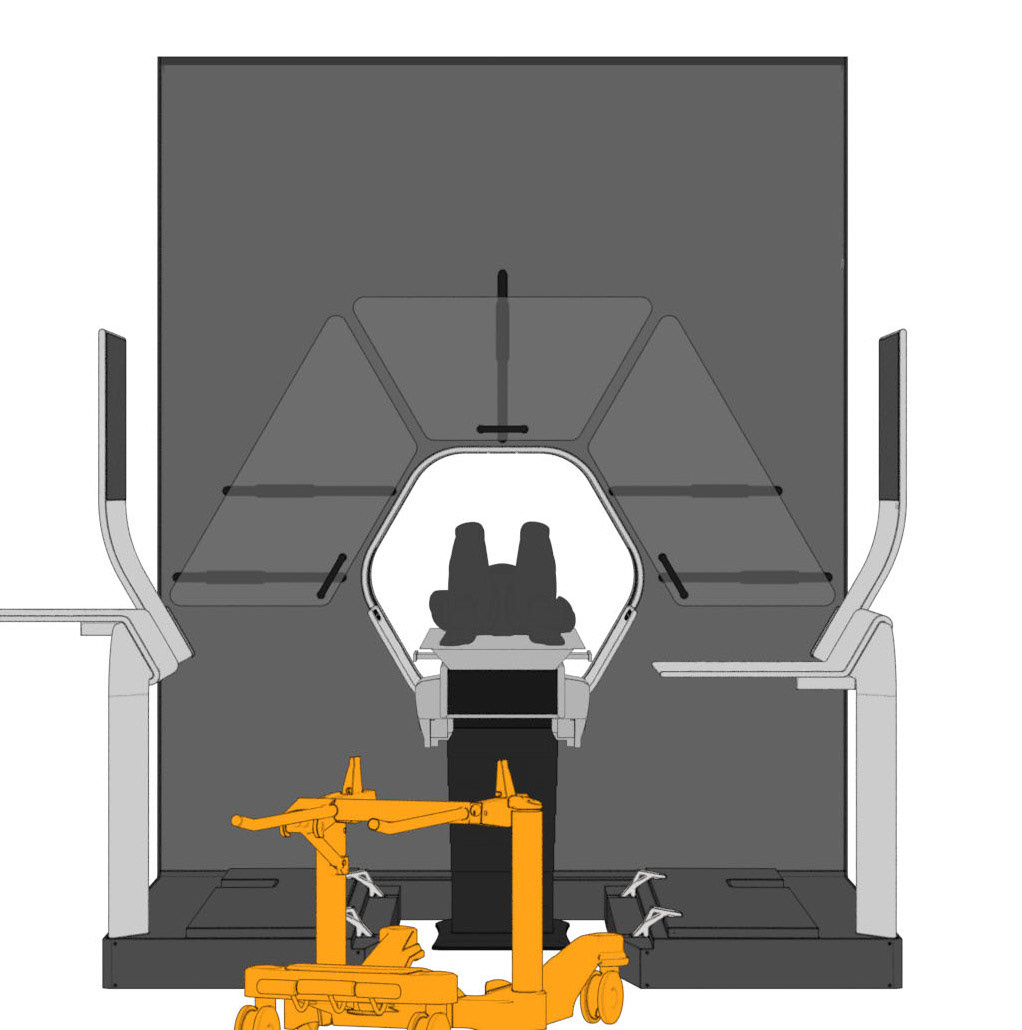

The central design feature is the hexagonal gantry opening. It provides space for the lamps and displays. The large fronts of the gantry offer space for a display of different coloured patterns and animations, which visualize the radiation. These can be individually selected and adapted together with the overall height of the gantry. The patterns pick up on the hexagonal shape of the gantry opening and set it off. To protect the interventionists from radiation, lead glass panels and a radiation protection tray are installed. The sliding lead glass panels allow individual adaptation to the patient and the interventionists working space. The tray serves to protect the abdomen and offers a lot of foot space as well as a front leaning aid for a safe stand.

Due to the new position and height of the gantry opening, the isocenter is shifted upward compared to conventional CT units. In order for the physician to operate as usual in the isocenter, his platform must also be shifted upward by this height difference. A review in VR showed that a platform height of 15cm provides the optimal comfort for the interventionalist.

The patient bench can compensate for the height difference of the isocenter by its height adjustability. Even in transport mode, the patient bench can be inserted into the opening without collision. Thus, no elevation is necessary for the couch.

Various tables can be suspended on the railing. This enables the individual positioning of surgical instruments and devices. To relieve the interventionists, it is also possible to lean against the railing, similar to a standing seat in a gondola or tram. In addition, the railing offers protection against a potential fall from the platform.